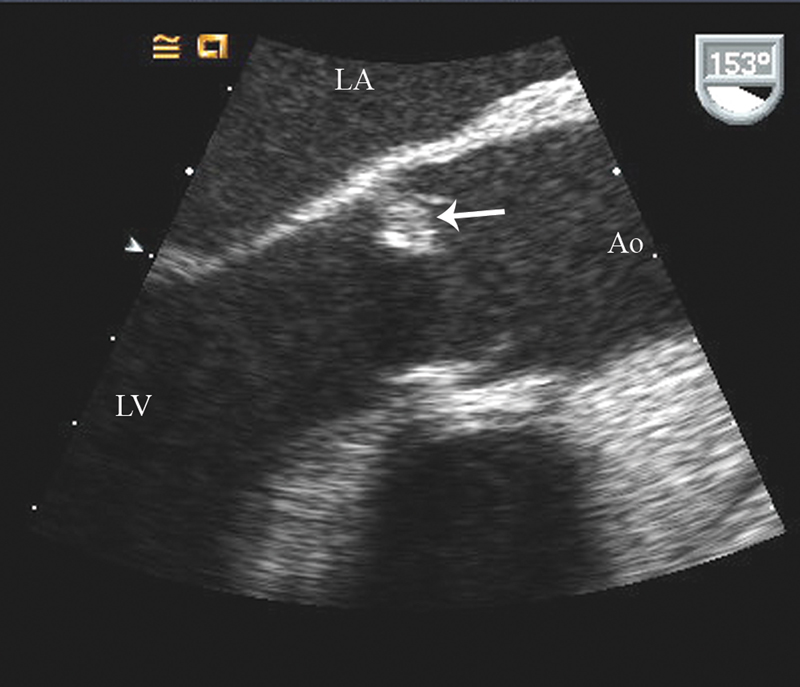

فحوصات تشخيصية لبعض امراض القلب والشرايين التاجية